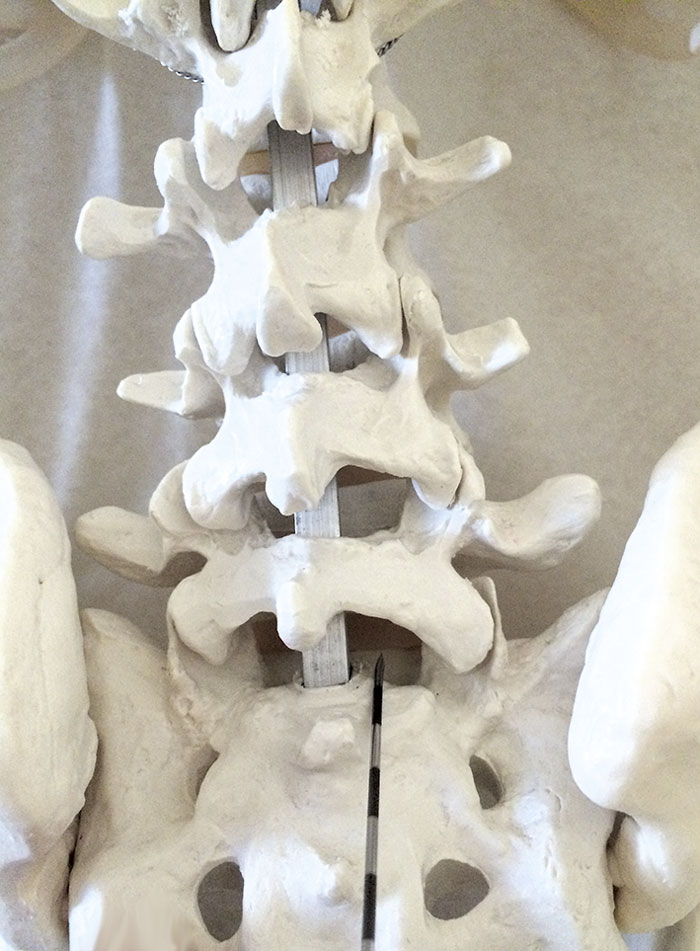

Vid interlaminära injektioner – samma teknik som används vid anestesi – sticker man i stället rakt bakifrån (Figur 2) och riktar nålen något lateralt, varvid läkemedlen sprids på antingen vänster eller höger sida och når flera nervrötter. Med den tekniken kan det dock vara svårare att nå fram till rotgangliet. Indikationerna är ofta en utstrålande radikulär smärta, men även vid till exempel spinal stenos brukar dessa injektioner kunna ge en bra smärtlindring, om än temporärt.

Figur 2. Nålspetsens placering vid interlaminär injektion.